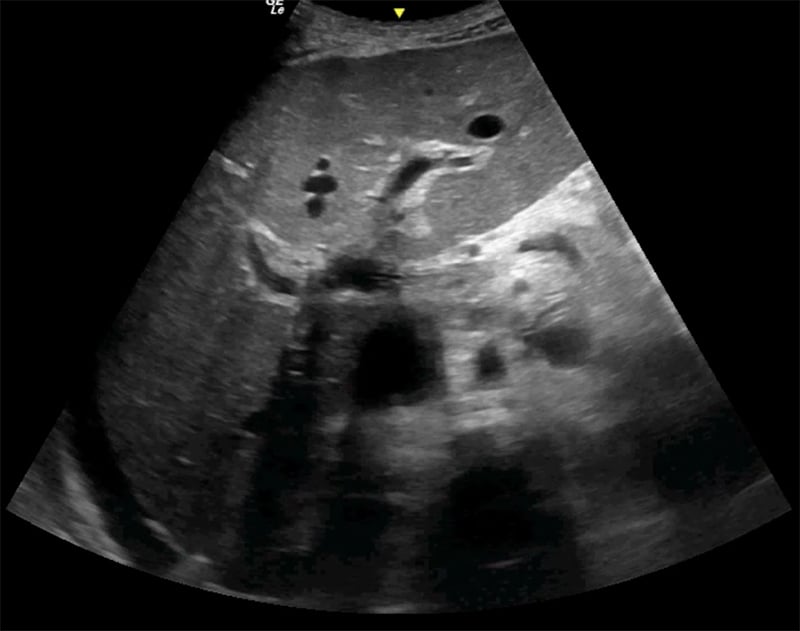

Figure 24A. Large pyogenic liver abscess with heterogenous material swirling inside the lesion, and “dirty shadowing.”

Figures 24B & 24C. Large pyogenic liver abscess with heterogenous material swirling inside the lesion, measuring >11cm in the long dimension (B) and >5cm in the shorter dimension (C).